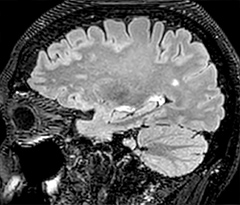

This is an example of acute ischemic stroke with distal occlusion of the right posterior cerebral artery. Note the improved visibility of the ischemic territory on the diffusion weighted image with high b-value. The 3D FLAIR shows a distal PCA occlusion. The fast SWIp depicts the thrombus on the isolated second echo image. The total scan time (including SmartBrain, preparations and a fast 3D T1w TSE Gd) is 8:00 minutes.